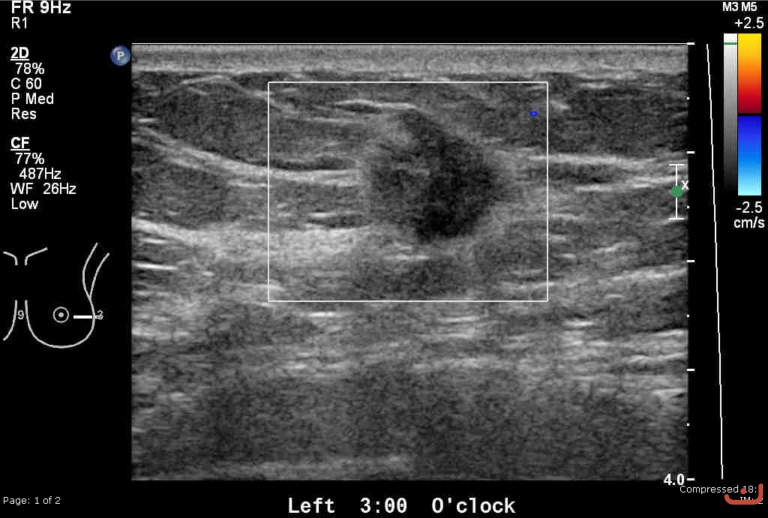

Malignant solid mass

Friday, 22 May 2015

215.84 KB (768 x 518 px)